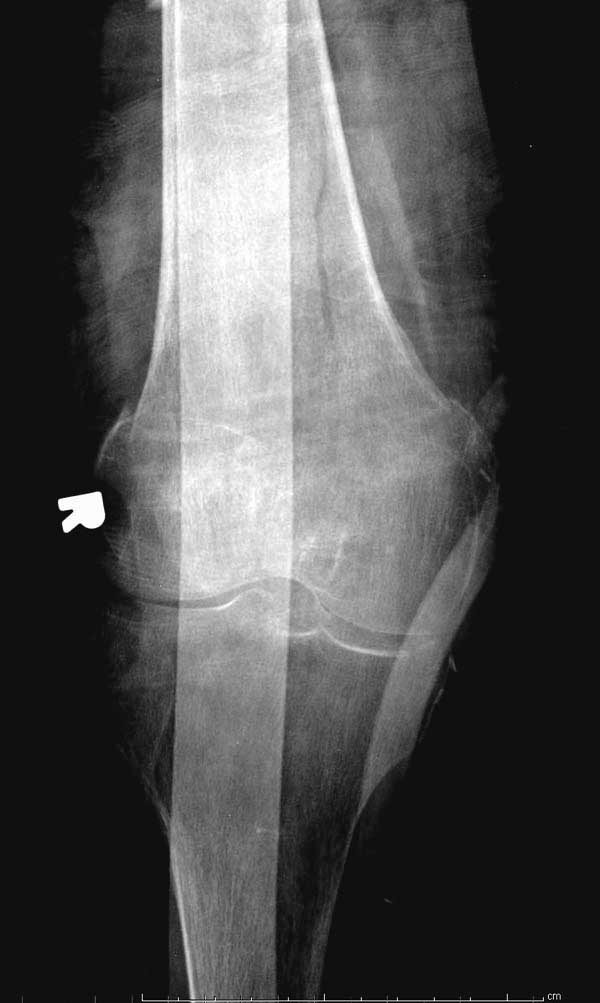

Первые снимки показывают технические погрешности установки DHS. Не была достигнута репозиция, конечность в флексии и шейка в ротации. Сегодня все меньше обращают внимание на параметры для оценки репозиции (S контуры Lowell в обеих проекциях и Garden Alignment Index, в норме 155 и 180 градусов), хотя такие простые тесты помогли бы дорепонировать смещение. Винт находится сзади в головке, что при нагрузке поменяет вектор и вместо компрессии в линии перелома срежет головку-Cut Out!

Обычно после чрезвертельных переломов, за исключением молодых, у пожилых остается нестабильность при движении. Часто падают и после 3х мес. в результате падения обнаружен перипротезный перелом (22-23), который зафиксирован Синтез пластиной.